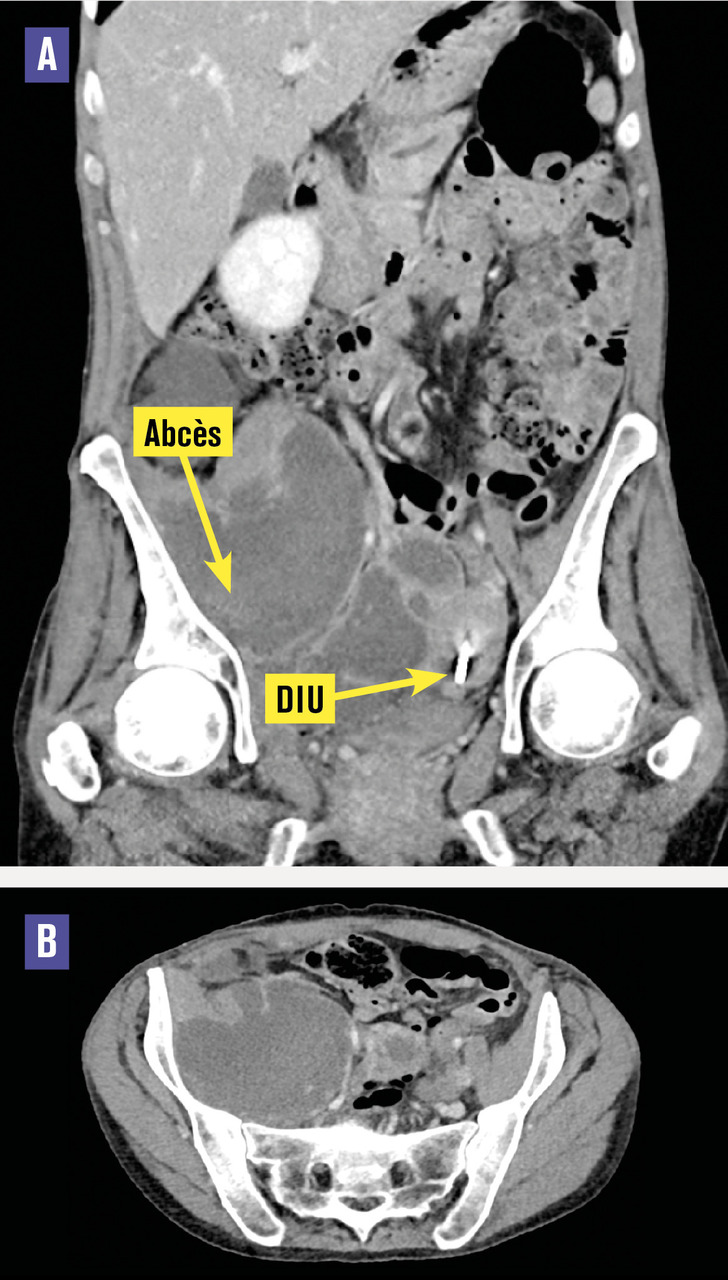

Cette femme de 48 ans était hospitalisée pour une fièvre associée à une douleur abdominale depuis plusieurs jours. L’examen clinique montrait une défense du flanc droit. Le toucher pelvien était normal chez cette patiente ayant un dispositif intra-utérin (DIU) au cuivre, posé il y a 5 ans. Il existait un syndrome inflammatoire biologique avec une CRP à 408 mg/L et une hyperleucocytose à 21 G/L. La tomodensitométrie (TDM) abdomino-pelvienne montrait une collection pelvienne multiloculée mesurant 30 × 37 mm communicant avec une seconde collection lobulée au sein du muscle ilio-psoas droit de 15 × 10 × 8 cm (fig. 1A et B ). Le drainage effectué sous contrôle radiologique permettait l’évacuation de 700 mL d’un liquide purulent. L’examen direct du DIU trouvait des bacilles à Gram positif branchés et la culture notait une flore vaginale avec des germes anaérobies, de nombreuses colonies d’Actinomyces turicensis (fig. 2 ) et de Streptococcus constellatus, présents également sur deux hémocultures. L’évolution était favorable sous amoxicilline (6 semaines).

L’actinomycose est une infection bactérienne invasive causée par des bactéries du genre Actinomyces, bactéries anaérobies à Gram positif filamenteuses branchées.1 Elles sont trouvées à l’état physiologique dans les flores commensales oto-rhino-laryngées et digestives. L’actinomycose pelvienne est rare (environ 5 % des actinomycoses), est favorisée par le port d’un DIU depuis 5 ans ou plus.2 La présentation est parfois atypique mimant un tableau tumoral pelvien. Le diagnostic peut être suspecté à l’imagerie mais repose sur les prélèvements bactériologiques, qui nécessitent des milieux de culture spéciaux et des temps de culture longs. Le traitement repose sur le retrait du DIU, le drainage chirurgical ou sous contrôle radiologique de l’abcès, et sur une antibiothérapie prolongée d’au moins 6 semaines par pénicilline (cycline en cas d’allergie). L’évolution est le plus souvent favorable.